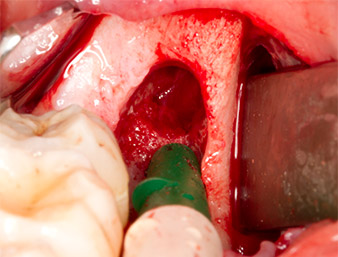

Con el fin de preparar el resto radicular de forma libre sin dañar el tejido, se utilizó otro inserto (Piezomed S2), que está indicado sobre todo para la preparación de la ventana lateral en los aumentos de la base del seno maxilar. Además, se utilizó la esfera diamantada para alisar los bordes óseos afilados (figuras 6 y 7). Todos los accesorios Piezomed se utilizaron con el ajuste estándar automático correspondiente sin función de refuerzo de la potencia.

Piezomed S2

Imagen 6: Con un inserto esférico diamantado (Piezomed S2) el resto radicular se preparó de forma libre con cuidado y los bordes óseos se alisaron.

resto radicular 38

Imagen 7: El resto radicular 38 aparece bien representado en su alvéolo para extraerlo a continuación.